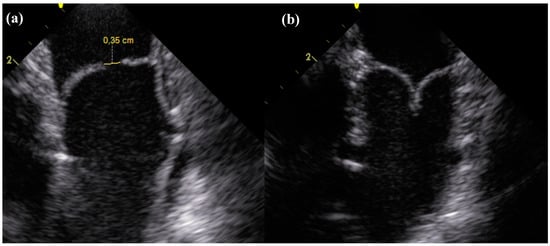

Figure 2.

Longitudinal section of the dTEHV during intracardiac echocardioraphy. (a) Coaptation deficit of 0.35 cm 24 weeks after implantation in a first generation dTEHV; (b) Coaptation 24 weeks after implantation in a second generation dTEHV (Coaptation was 0.5 cm).

Valve functionality directly after implantation as well as after 24 weeks shows substantial improvement from first to second generation dTEHV. Even after 52 weeks, 6 out of 9 second generation dTEHV still remaining in the experiment showed only mild insufficiency (median insufficiency grade: Severe), whereas for the first generation dTEHV 4 out of 5 valves showed severe regurgitation at 24 weeks already (median insufficiency grade: Severe), mainly due to coaptation deficit. (Figure 2 and Figure 3).